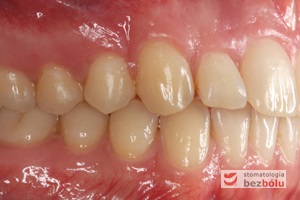

Młody 28-letni, pogodny, stale uśmiechnięty pacjent zgłosił się celem korekcji wad zębowych ograniczających pełną ekspresję uśmiechu. Głównym problemem był dodatkowy siekacz boczny (dwójka) po stronie prawej w łuku górnym. Dodatkowy ząb spowodował stłoczenia pozostałych zębów w łuku górnym oraz przesunięcie linii pośrodkowej. Obliczenia dostępnego miejsca dla siekacza bocznego wpłynęły na wybór zęba przeznaczonego do ekstrakcji. Usunięto dwójkę ustawioną dowargowo, zaś jej „siostrę bliźniaczkę” skierowaną w stronę podniebienia wprowadzono do łuku zębowego w drodze leczenia ortodontycznego. Problemem było szczelne zamknięcie szpary poekstrakcyjnej z powodu nadmiaru miejsca w kości. Wyrównano linię pośrodkową. Leczenie przeprowadzono jednym łukiem ortodontycznym górnym, dolny łuk zębowy nie wymagał założenia aparatu. Po zdjęciu zamków korekcję detali przeprowadzono z użyciem pozycjonera wykonanego w technice termoformingu. Stabilizację efektów leczenia zapewnił stały retainer klejony do powierzchni podniebiennych siekaczy górnych.